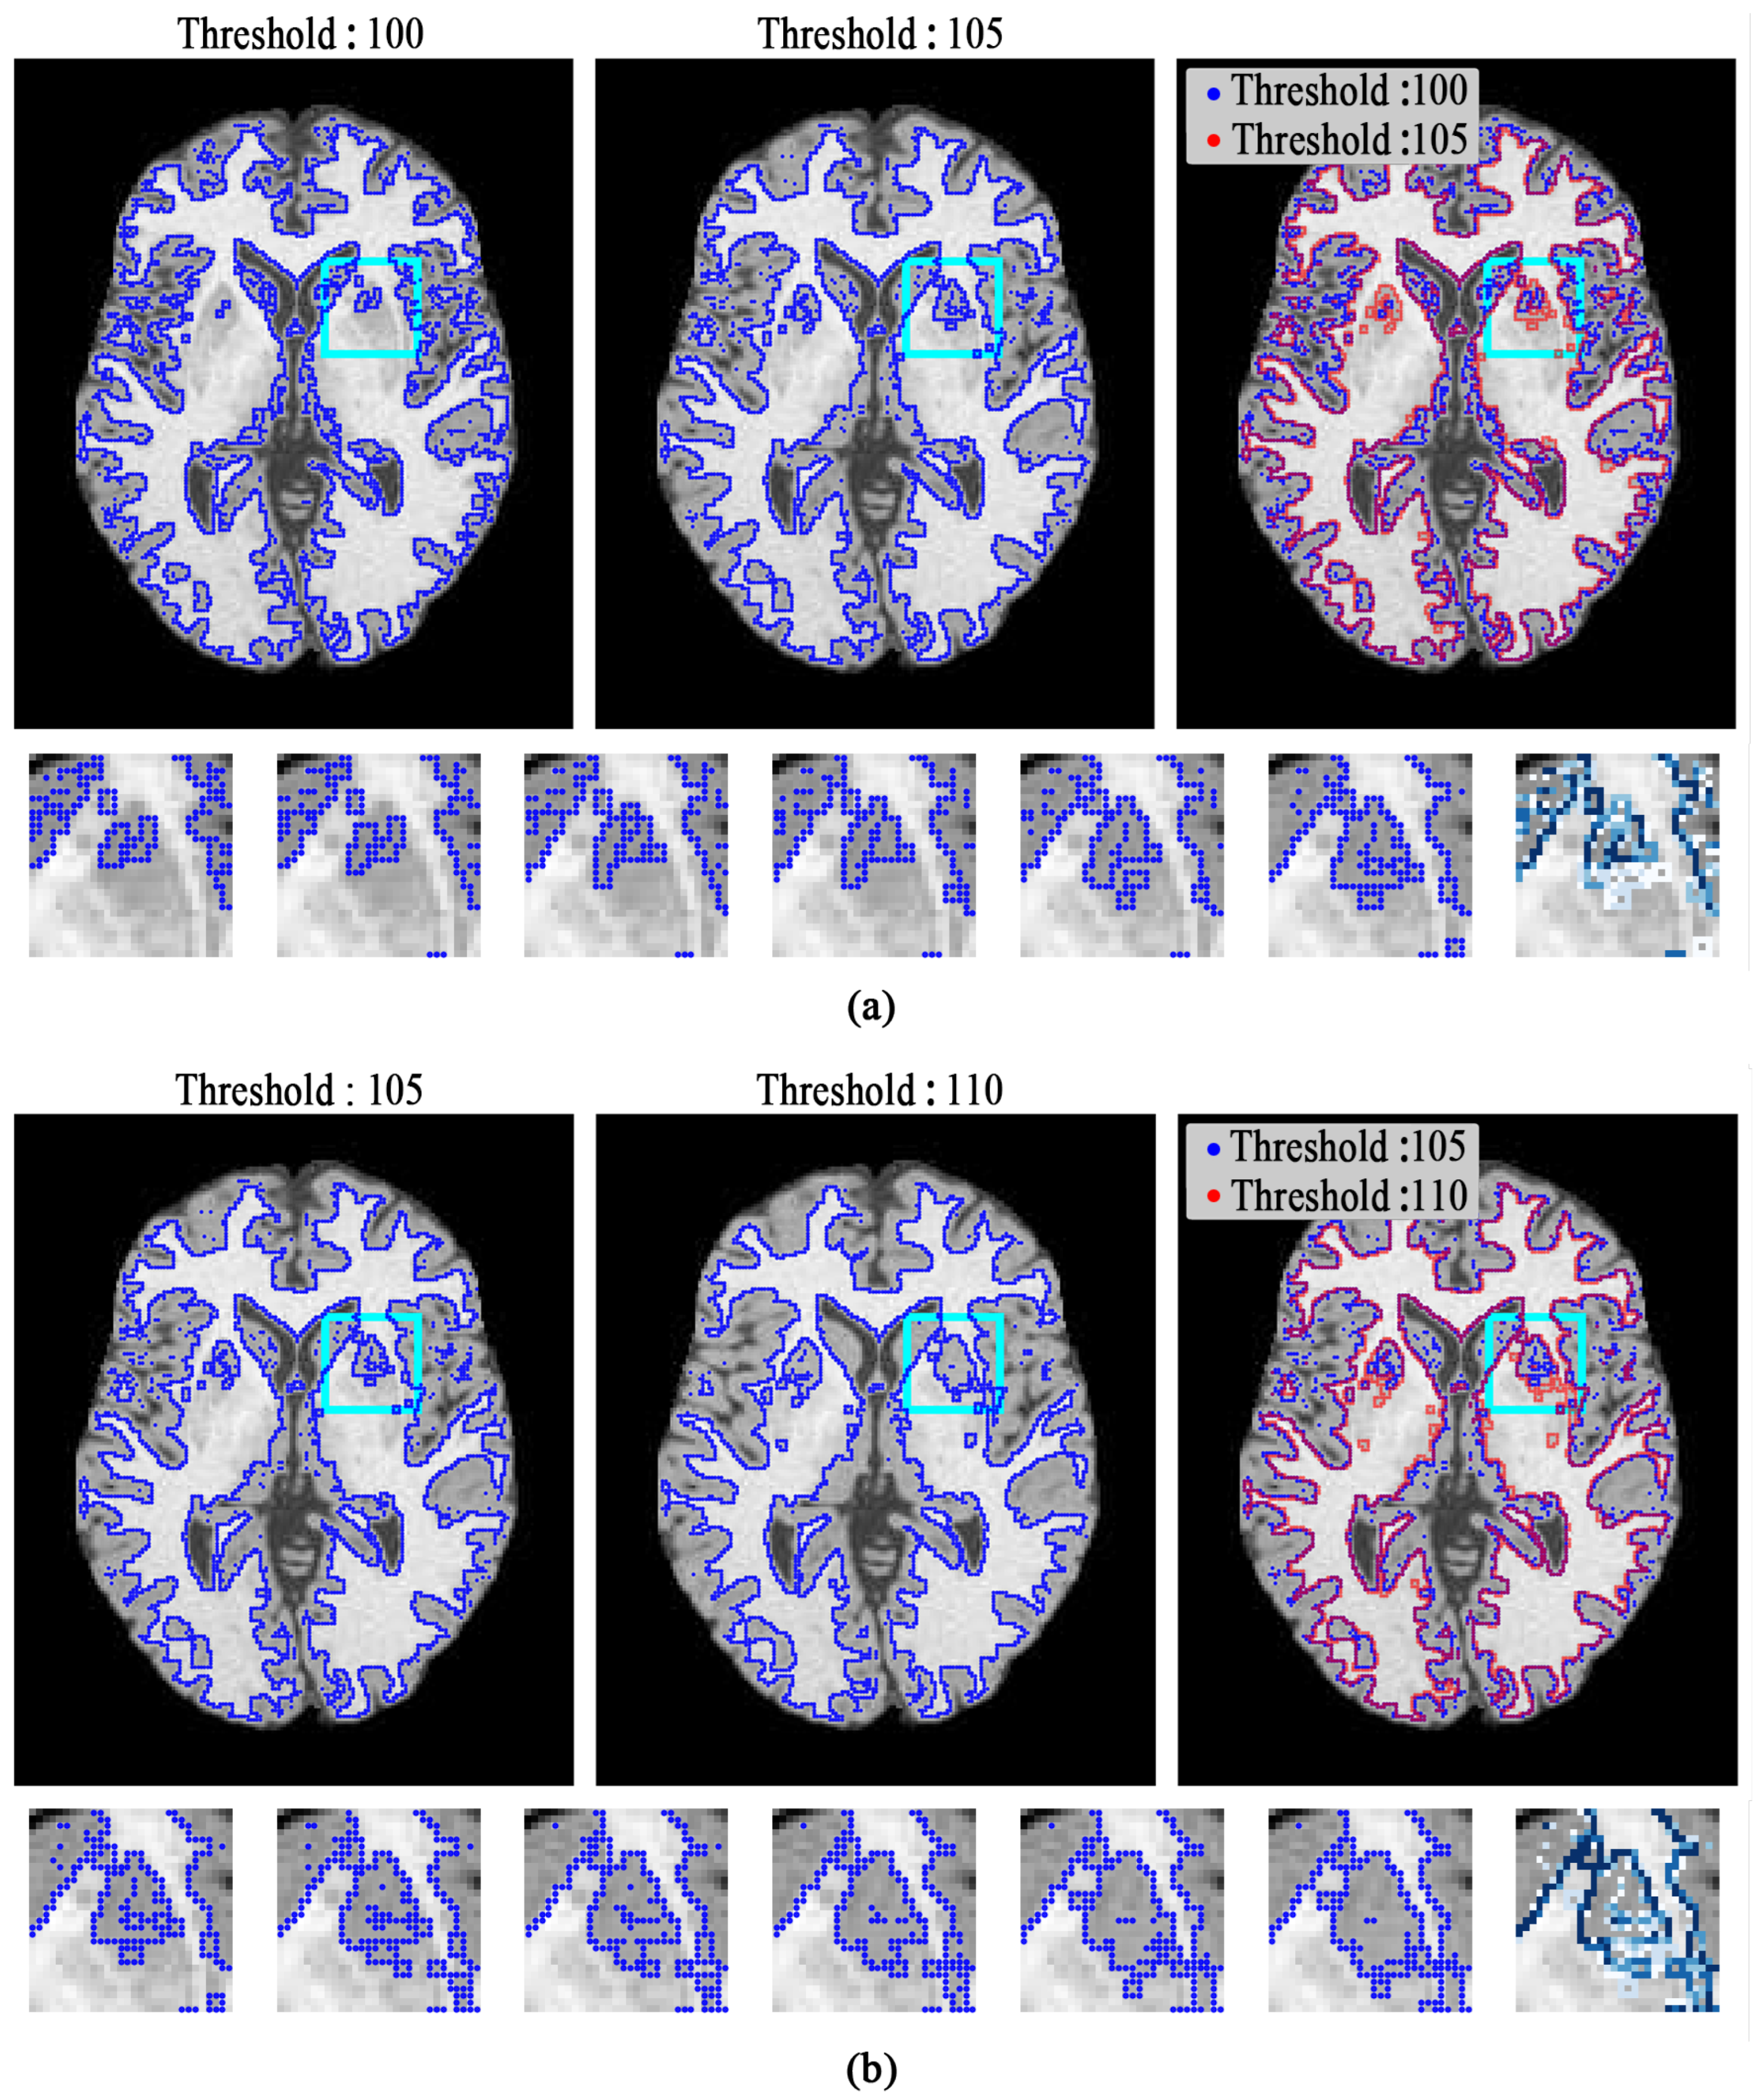

Figure 10 demonstrates the results of image thresholding on some slices taken from the BrainWeb and MRBrainS13 datasets. A comparison revealed that the segmentation achieved by the Otsu method was the worst, showing poor stability in the results. Cauchy-TB and Tsallis-BE were more similar to the ground truth, with the Tsallis-BE method performing well but being slightly inferior to ours in some perceptible details.

Figure 10.

The results of image thresholding by the Cauchy-TB, Otsu, and Tsallis-BE methods. For both the left (BrainWeb) and right (MRBrainS13) groups, the columns from left to right represent the original slice; the ground truth (GT); and the results of Otsu, Cauchy-TB and Tsallis-BE, respectively.